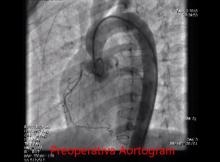

A 12-year-old boy was diagnosed with supravalvular aortic stenosis. He underwent an aortoplasty with Brom’s technique, which involved enlarging all three sinuses with pericardial patches. This video is a step-by-step illustration of the procedure.